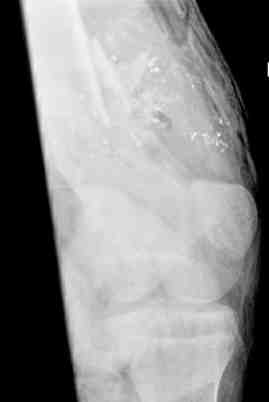

Выше представлены рентгенограммы открытого оскольчатого перелома нижней трети голени

X-rays of Compound Comminuted # Distal/3 Lt Tibia

Операционные снимки перед и после наложения аппарата Илизарова

In operation room before and after Ilizarov apparatus has been applied